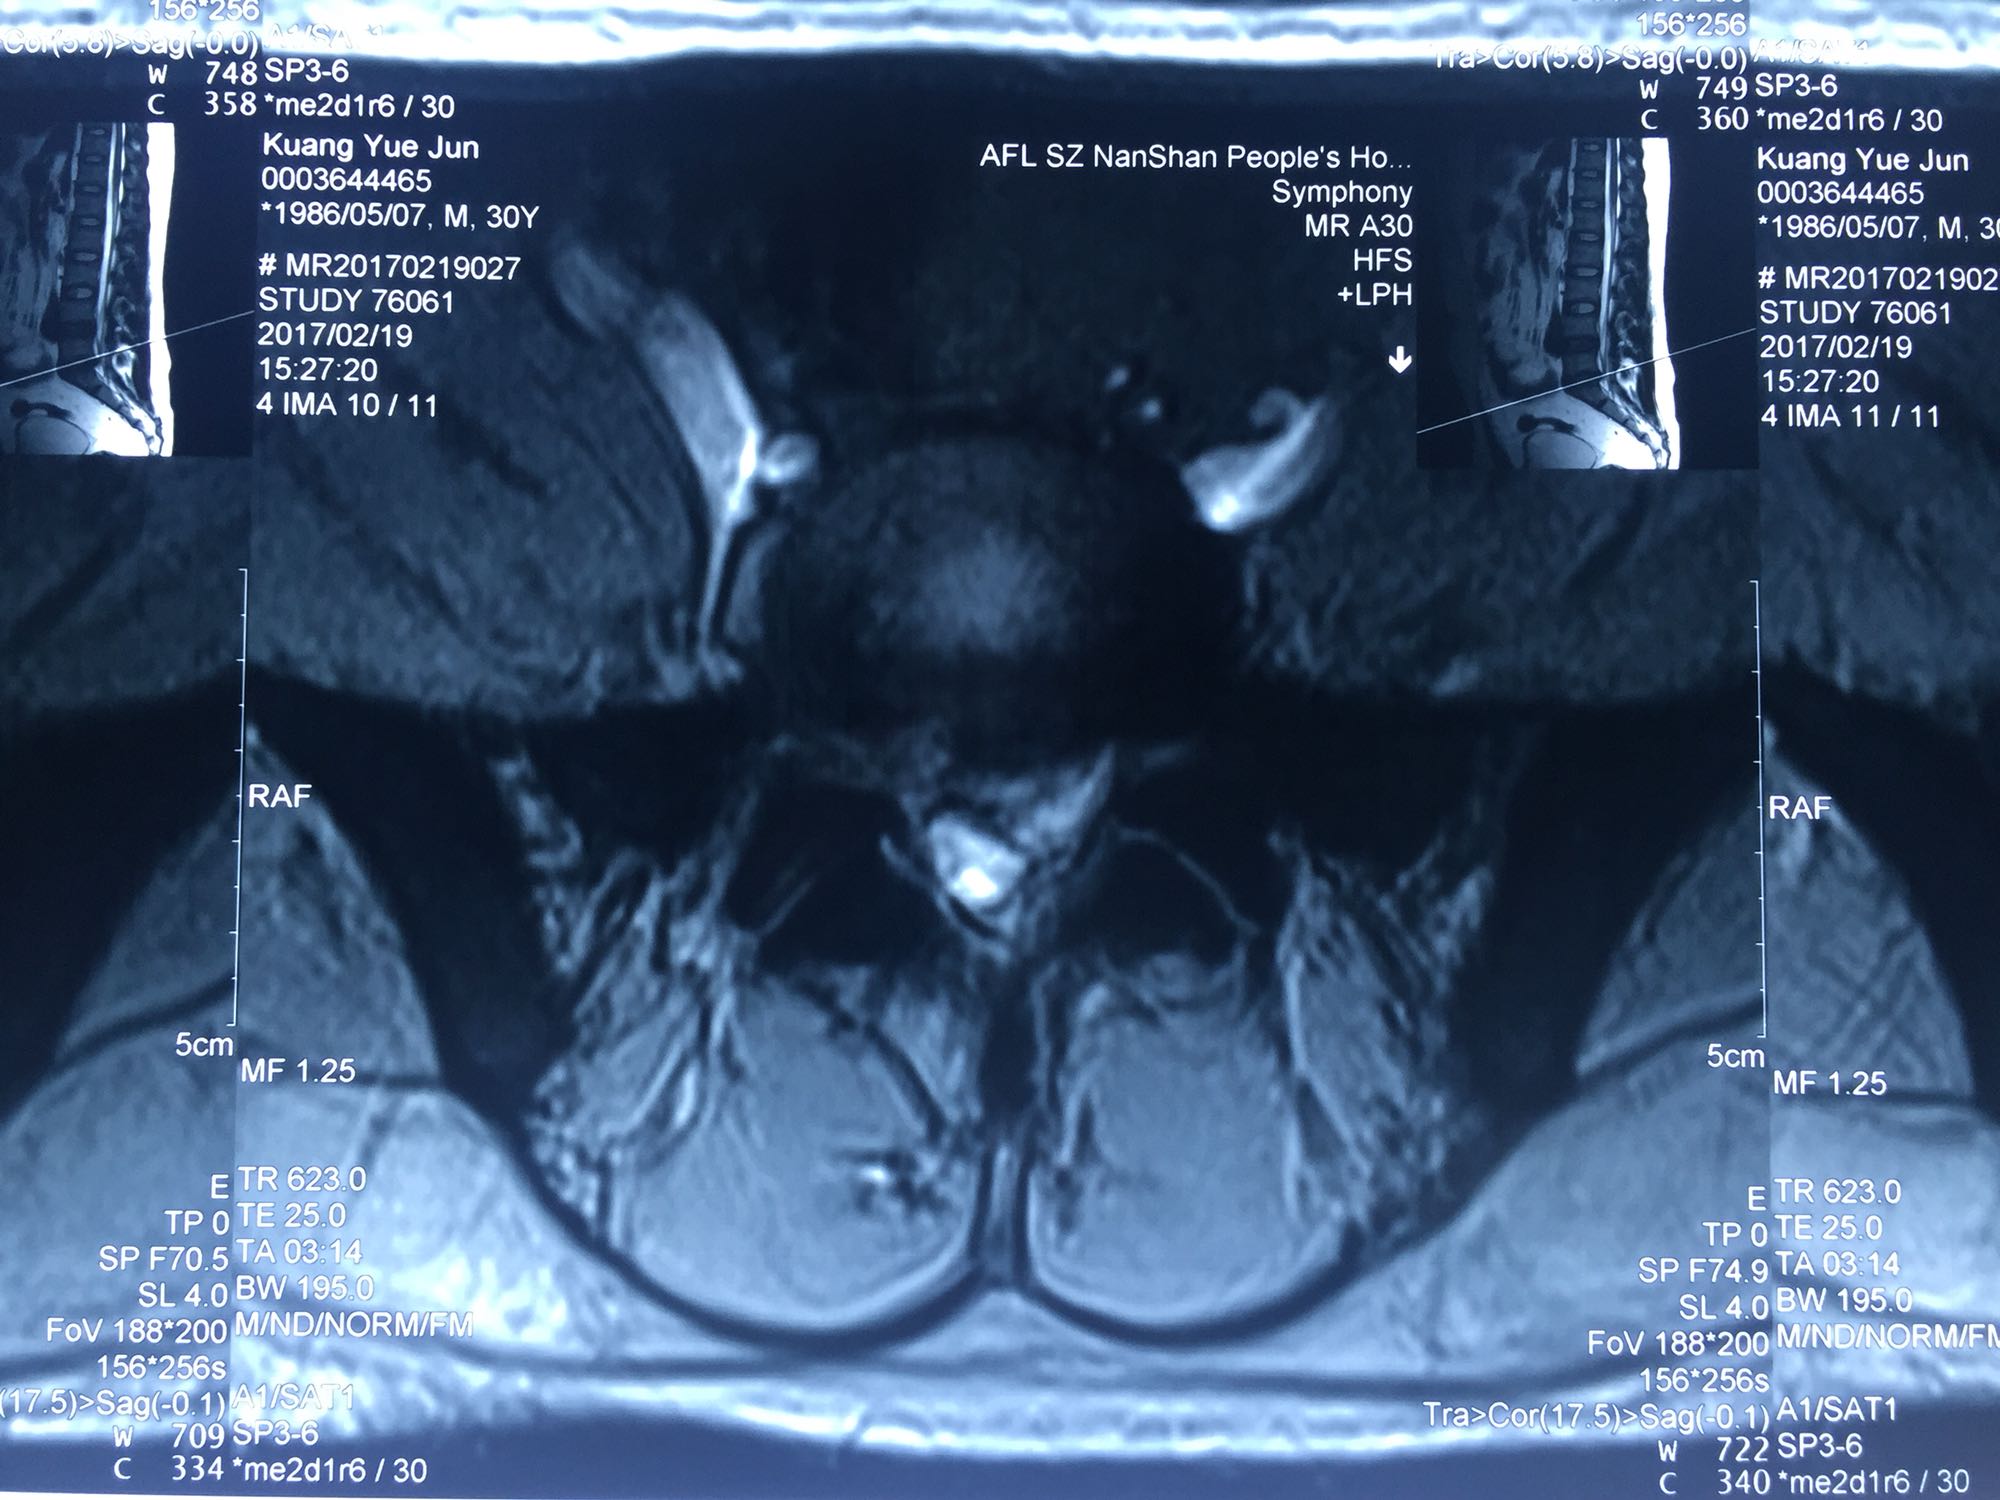

椎间孔镜下腰5骶1椎板间隙入路髓核摘除术

腰骶部肌紧张,腰5骶1棘间及左侧椎旁有压痛及放散痛,左侧坐骨神经出孔处有压痛及放散痛,左侧足背外侧及足底部皮肤感觉麻木,左侧直腿抬高试验阳性(30度)。

诊断:腰5骶1椎间盘突出症 治疗方案:椎间孔镜下经椎板间入路髓核摘除术

术后患者疼痛完全消失